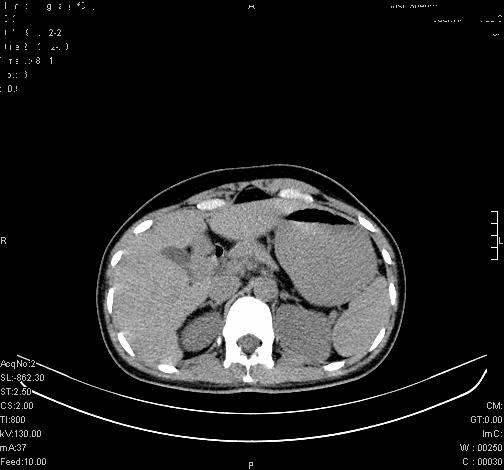

患者为年轻女性,查体发现右侧肾上腺囊性占位。无临床体征。

这么漂亮的图像,一看一目了然。典型的右侧肾上腺囊肿,周围有钙化。感谢搂主!

这么明显的弧形钙化,多考虑包虫病所致的寄生虫性囊肿。

右侧肾上腺囊性密度灶囊壁有钙化。考虑肾上腺囊肿,结核?

右侧肾上腺囊肿,周围有钙化。